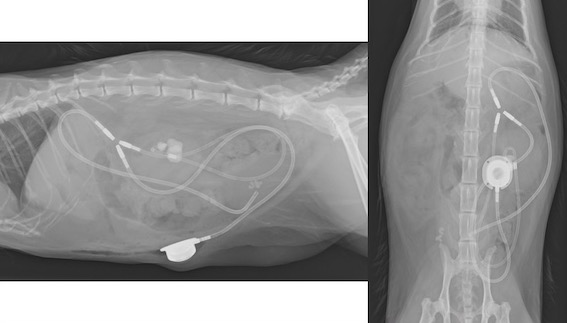

手術後のSUBシステムの位置関係はこのようになります。

SUBシステム(皮下尿管バイパスシステム)とは、

近年開発されたもので、腎臓と膀胱を直接カテーテルでつないでしまうというものです。